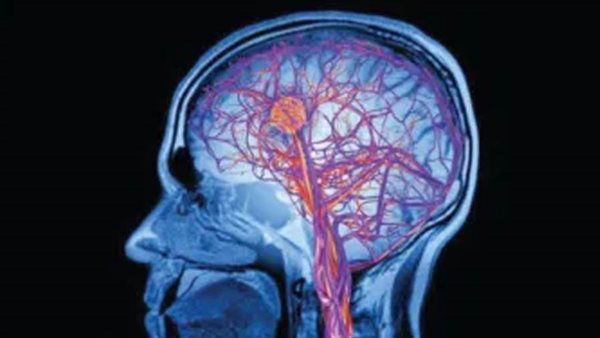

شارك في الدراسة 20 مريضًا من مرضى اضطراب النوم تتراوح أعمارهم بين 54- 77 عامًا، و25 شخصًا يتمتعون بصحة جيدة تتراوح أعمارهم بين 58-76 عامًا، وتمت مراقبتهم في مختبر النوم، لقياس النشاط الكهربائي في الدماغ، وحركات العين، ونشاط العضلات، والنشاط الكهربائي في القلب أثناء النوم، وكذلك اختبار المرضى والأشخاص الضابطين معرفيًا وفحص التصوير بالرنين المغناطيسي.

وكشفت النتائج عن انخفاض تدفق الدم واضطرابات التدفق في الأوعية الدموية الصغيرة في الدماغ لدى المرضى مقارنة بالمجموعة الضابطة، وعكف الباحثون على دراسة ما إذا كان انخفاض تدفق الدم في الدماغ يتدهور بمرور الوقت وكيف يرتبط بأعراض مرض الشلل الرعاش، وهو ما يمكن استخدامه كطريقة للتنبؤ بالمرض لدى المرضى الذين يعانون من اضطرابات النوم من أجل منع الأعراض بعد ذلك في مرحلة مبكرة.